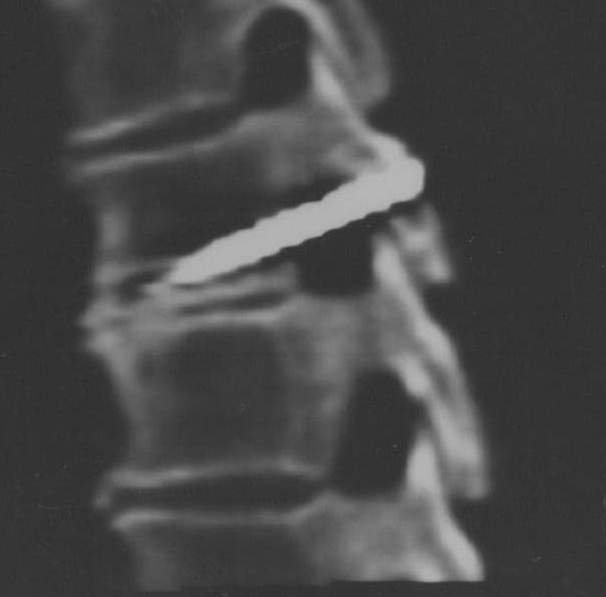

...В проекции ТН 5-ТН6 выявляется инородное тело - шуруп длиной до 3,7 см, шириной до 0,65 см, без шляпки по задней поверхности. Острие шурупа направленно кпереди переднего отдела тела… Судить о состоянии спинного мозга и корешков не представляется возможным из-за наличия выраженных артефактов от шурупа. Изменений в мягких тканях задней поверхности спины на этом уровне не отмечено.

Заключение: инородное тело - шуруп, проходящий через дужку, костно-мозговой канал и тело Th5 справа.

Томские медики поправили москвичей. Гвоздь оказался больше похож на шуруп - за три месяца на нем выросли зубчики. Да и в диаметре он увеличился в полтора раза. А самое главное – зубчатый предмет оказался полностью внутри тела позвонка. В одном миллиметре от спинного мозга…